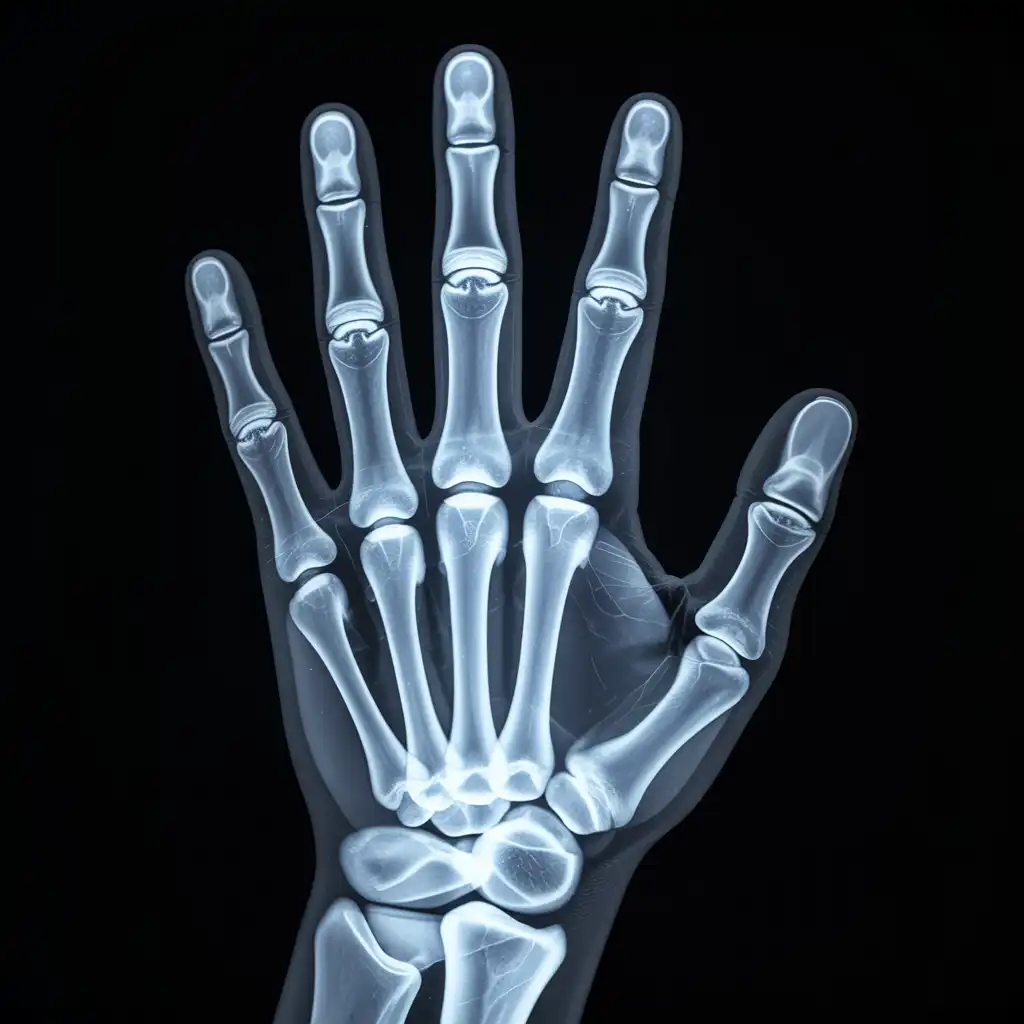

Una lastra a domicilio è una radiografia eseguita direttamente a casa del paziente, grazie all’intervento di un tecnico sanitario qualificato dotato di apparecchiatura digitale portatile.

L’esame viene effettuato sul posto, senza necessità di spostare la persona dal letto o dalla poltrona, e garantisce una qualità diagnostica paragonabile a quella di un reparto ospedaliero.

Una volta acquisite, le immagini vengono trasmesse al medico radiologo, che le analizza e redige il referto in tempi brevi.